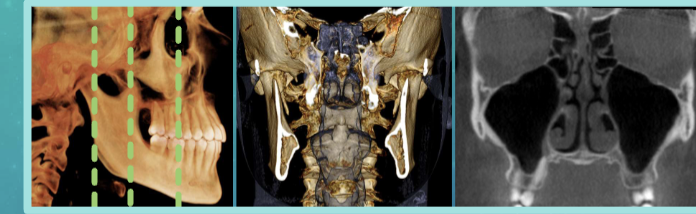

CBCT scan - cone beam, computed tomography

cone-shaped x-ray beam, rotates around the patients head

scan time 7-30 seconds

contrast res > bit depth

spatial res - voxels 3-dimensional pixels

traditional medical CT

computed tomography

fan shaped x-ray beam rotates around pt

rotations move down the section of anatomy of interest

layers/ slices of images are stacked with software during image reconstruction

Coronal plane

axial plane

sagittal plane

anatomical/ orthogonal projections

multiplanar reconstruction/ reformation

volumetric rendering

commons uses of 3D imaging

improved interpretation diagnosis and treatment planning of dental care

implant placement

extraction or exposure of impacted teeth

definition of anatomic structures

endo assessment

airway and sinus analysis

eval of TMJ disorders

ortho eval

eval of lesions/ abnormalities

trauma eval

advantages of CBCT

lower radiation dose than CT

easy to save and share date

brief scanning tim e

accurate anatomical images

disadvantages of CBCT

patient movement, small FOV could limit view, cost, training, exposure